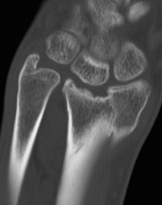

CT